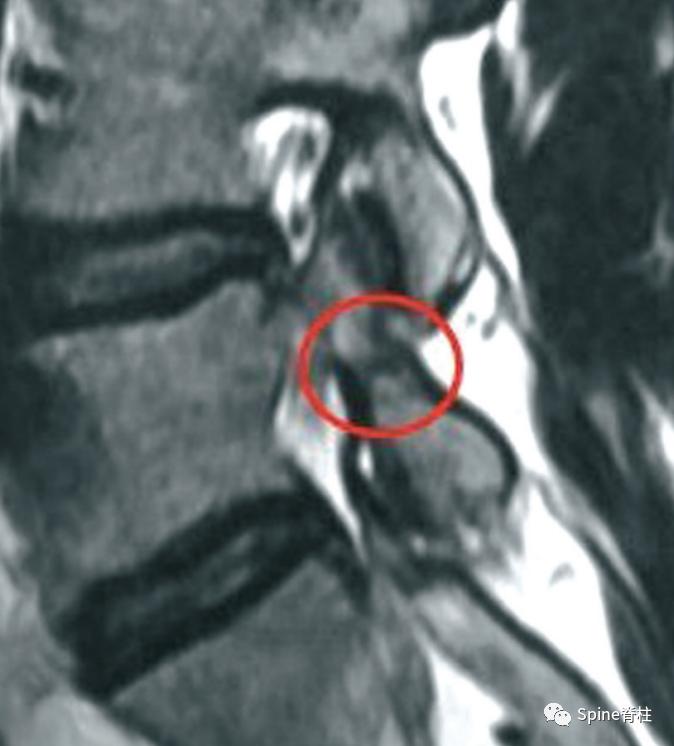

MRI提示的峡部裂(红圈)